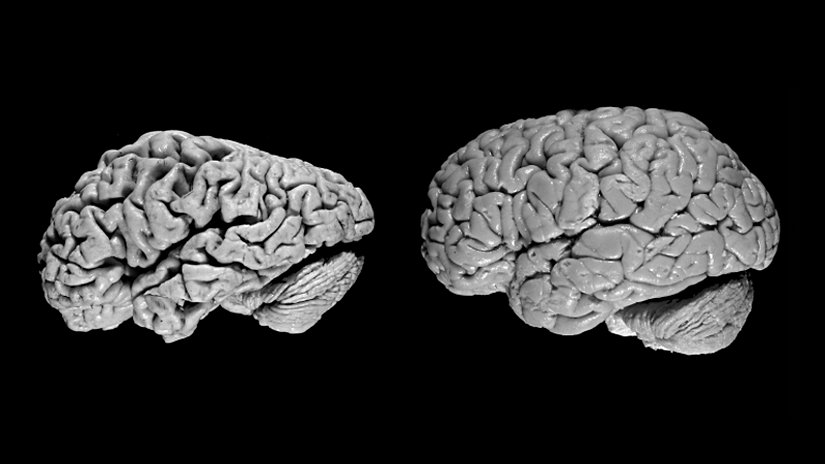

Hasar en şiddetli şekilde beyinde hafızayı kontrol eden bölgede başlar, ancak bu süreç ilk semptomlardan yıllar önce açığa çıkar. Nöron kaybı, beynin diğer bölgelerine bir miktar öngörülebilir bir şekilde yayılır. Hastalığın geç evresinde ise beyin önemli ölçüde küçülür. Araştırmacılar iki proteinin hastalık üzerinde rolüne odaklanmıştır.